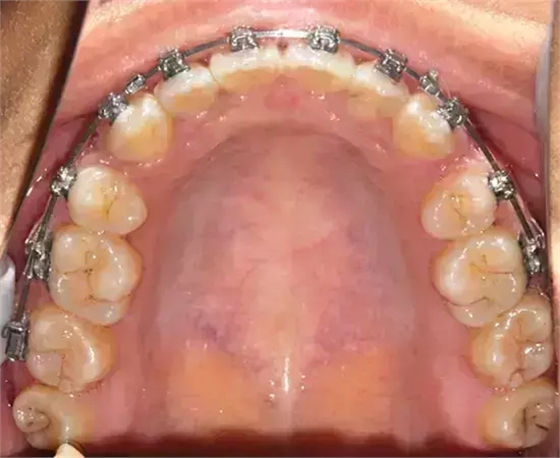

患者側(cè)面凸,鼻唇角較銳,笑時(shí)露齦笑明顯上下牙列擁擠,磨牙尖牙Ⅱ 類關(guān)系,3 度的深覆牙合,上頜中切牙伸長內(nèi)傾拔除上頜雙側(cè)的第一前磨牙,先粘上頜高轉(zhuǎn)矩的自鎖托槽排齊牙列,唇向開展上頜切牙,有一定的覆蓋,粘下頜標(biāo)準(zhǔn)轉(zhuǎn)矩托槽,上頜 1, 2 之間植入種植支抗壓入,同時(shí)后牙 5, 6 之間植入種植支抗內(nèi)收前牙,打開咬合關(guān)閉間隙。治療關(guān)鍵:前牙轉(zhuǎn)矩的控制第 1 個(gè)月 上頜粘上 Damon Q 高轉(zhuǎn)矩托槽,上 .014 熱激活 NiTi 絲。第 3 個(gè)月 上換 .014 x .025 熱激活 NiTi 絲。第 5 個(gè)月 上頜基本排齊,覆蓋增大,上換 .017 x .025 NiTi絲,下頜粘托槽,下 .014 熱激活 NiTi 絲。第 7 個(gè)月 上 .017 x .025 NiTi 絲加搖椅,下?lián)Q .014 x .025 熱激活 NiTi 絲第 9 個(gè)月 上頜換 .019 x .025 NiTi 絲加搖椅,下頜換 .017 x .025 NiTi 絲第 11 個(gè)月 下頜換 .019 x .025 加搖椅,上頜 1, 2 之間, 5, 6 之間植入種植釘,下頜出現(xiàn)散隙。第 13 個(gè)月 上頜換 .019 x .025ss 加搖椅,前牙種植釘用 Power Chain 壓低前牙(每側(cè) 100g),后牙種植釘關(guān)閉間隙(每側(cè) 150g),下?lián)Q .019 x .025ss,Power Chain 關(guān)閉間隙。第 19 個(gè)月 上頜前牙基本壓低到位去除前牙種植釘,繼續(xù)用關(guān)閉間隙,下頜散隙關(guān)閉。

第 22 個(gè)月 上頜覆蓋變小,去除 5, 6 之間種植釘,后牙前移關(guān)閉間隙。第 30 個(gè)月 患者未配合中線牽引,下中線仍有 1mm 右偏,患者對矯治效果滿意要求拆除,拆除固定矯治器,取模制作壓模保持器。 1.骨性 Ⅱ 類的患者內(nèi)收前牙時(shí)需對上頜前牙的轉(zhuǎn)矩進(jìn)行較好的控制才能獲得良好的面型和唇部形態(tài)。 2.露齦笑的患者治療前要分析其病因是唇、牙齦、牙齒、牙槽骨、上頜骨或多種因素結(jié)合,再制定矯治方案。 3.Ⅱ 類第二分類伴露齦笑的患者的上頜前牙移動軌跡是唇向開展-壓低-整體內(nèi)收。 4.Ⅱ 類第二分類牙齒舌傾比較厲害的情況,上頜中切牙慎用樹脂咬合墊。 5.壓低前牙或控根移動時(shí)容易發(fā)生牙根的吸收,需輕力緩慢的移動。